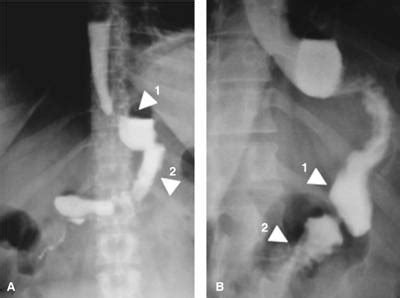

Figura 2: Anatomía Postquirúrgica de BPGYR

La anatomía postquirúrgica de la BPGYR en un paciente de 42 años, 24 horas después de la cirugía, muestra un adecuado paso del medio de contraste del esófago distal hacia el reservorio gástrico (aproximadamente 30 mL). No se evidencia fuga ni comunicación anómala. Tampoco hay signos de fugas o estenosis en la anastomosis gastroyeyunal. Se observa tránsito normal del medio hidrosoluble a través del asa alimentaria y opacificación completa del intestino delgado distal.

Figura 3: Anatomía Postquirúrgica de la GVM

La anatomía postquirúrgica de la GVM en un paciente masculino de 51 años, 24 horas después del procedimiento, revela un paso adecuado del medio de contraste hidrosoluble a través de la unión esofagogástrica. El estómago se presenta tubular, largo y delgado, sin evidencia de fugas o torsión. Se observa un vaciamiento gástrico normal y paso del contraste hacia el duodeno e intestino delgado.

Figura 4: Anatomía Postquirúrgica de BPGUA

La anatomía postquirúrgica de la BPGUA en una mujer de 38 años, 24 horas después de la cirugía, muestra el paso adecuado del medio de contraste hidrosoluble del esófago distal al reservorio gástrico. No se observa dilatación del reservorio ni fugas en el sitio de la anastomosis. Se aprecia la opacificación del asa eferente y aferente; esta última es esperada por reflujo retrógrado y normalmente desaparece con las ondas peristálticas.